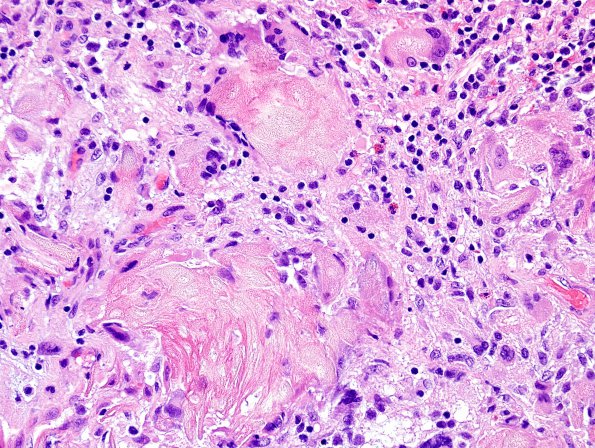

Craniopharyngioma, adamantinomatous

Reaction to extracellular keratin (H&E).